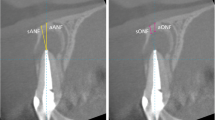

The arch form selector tool was centred throughout the middle of the arch in the coronal plane at the cement-enamel level selecting the centre of the nerve canal of single root teeth and the middle of the interradicular septum of multirooted teeth (Fig. 1). The thickness of the alveolar bone was measured after selecting the cross-sectional image made at the midpoint of the tooth, at which the centre of the root canal passes, parallel to its long axis (Fig. 2). To perform the measurements, sagittal scans from the reconstructed data were selected, resulting in images where the entire root and cementoenamel junction (CEJ) were present for single rooted teeth. Two different slices were selected for multirooted teeth, one which passed across from the apex of the mesiobuccal and the distobuccal root. The long axis determined the slice. The captured images had a resolution of 72 pixels/inch and were saved with the standard zoom of Planmeca Romexis [20] viewer and exported to Photoshop CS5 to be measured. All the images had a lateral ruler which served to the surgeons for calibrating the measurements made on the photo editor to the distance at the DICOM images.

The thickness of the buccal bone wall was measured in a sagittal slice, perpendicular to the long axis of the root (defined by the line from the incisal border to the apex) at several points (Fig. 2):

A:

Thickness at the first top coronal part of the buccal crest,

B:

Thickness 4 mm upper from the point A.

C:

Thickness at the apex from the apical constriction to the buccal wall.